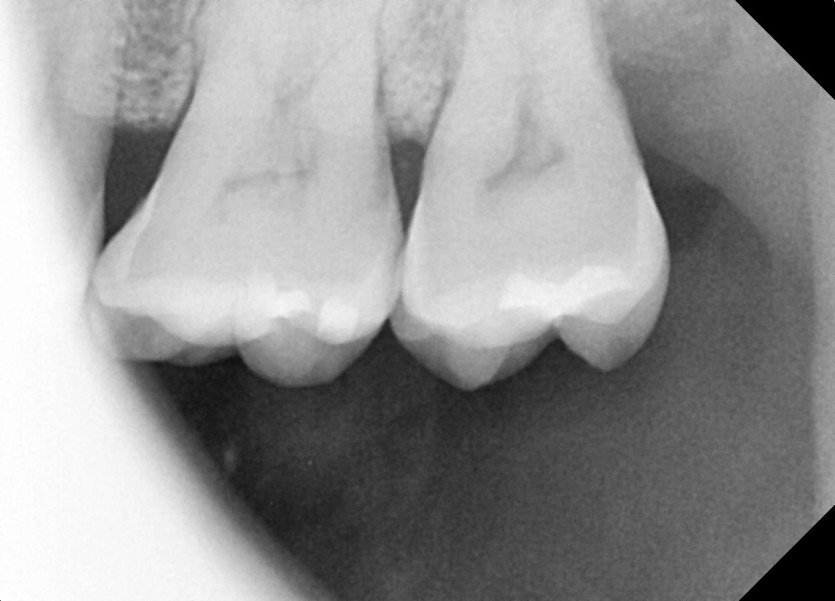

#28,38,48 사랑니 발치

구강 외과 전문의가 당일 발치했습니다.